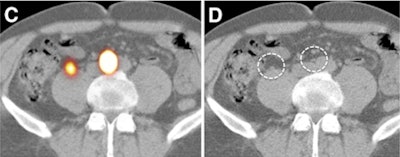

| Transverse SPECT/CT image (C) shows two sentinel nodes displayed in yellow. CT image (D) shows medial sentinel node corresponding to small lymph node ventral to area between aorta and cava, whereas lateral node is in area ventral to psoas muscle (circles). |